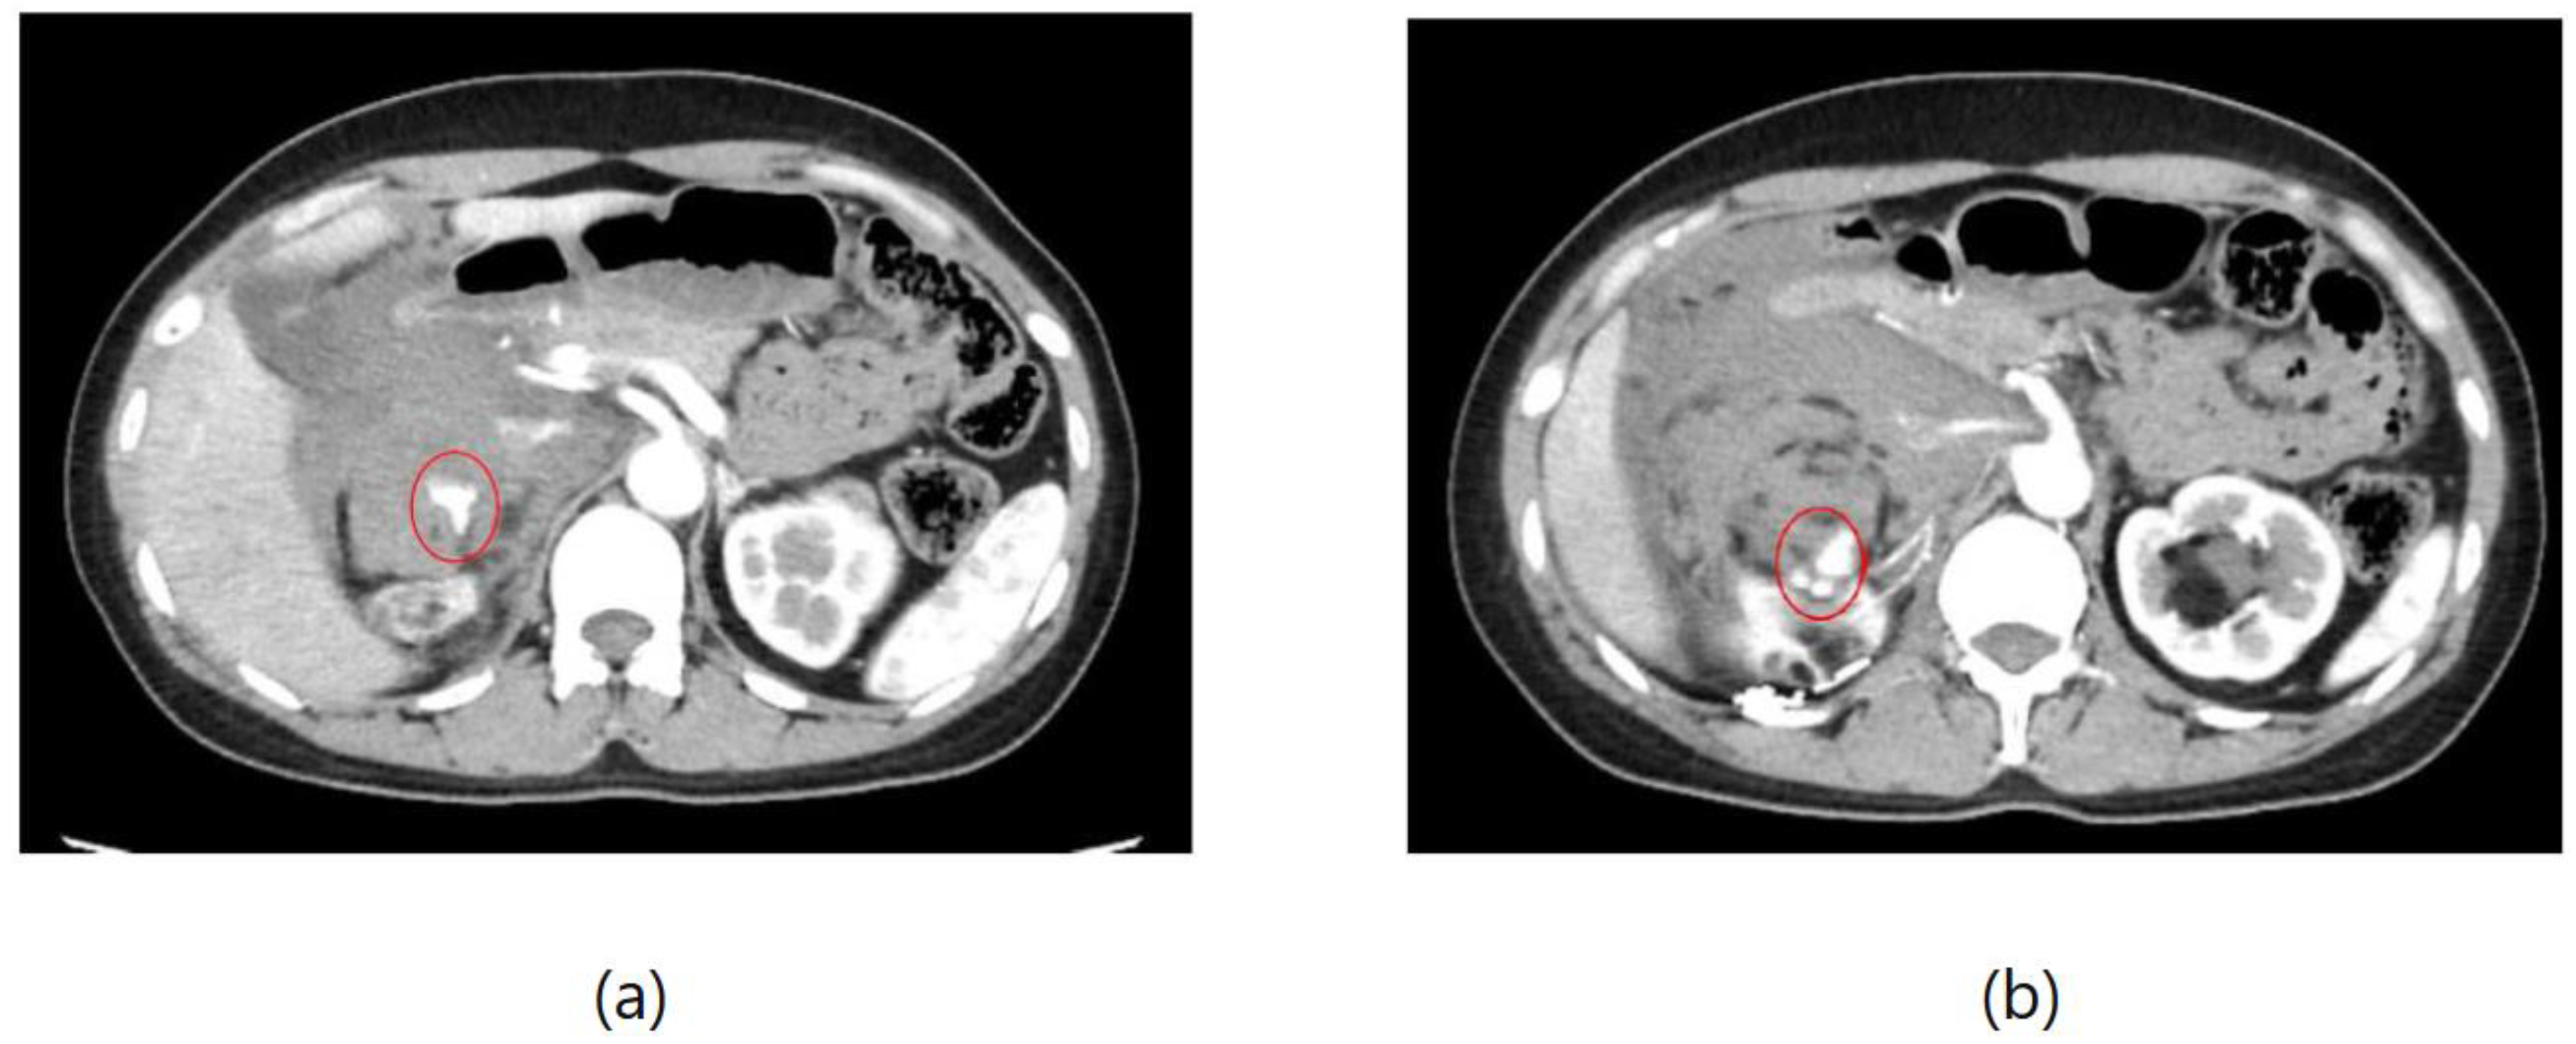

As an example, Figure 1 shows extravasation, or bleeding, from a polycystic kidney. Identifying the precise bleeding site on the computed tomography (CT) image presented a challenge. However, upon reviewing the angiography findings, it became evident that the bleeding originated from the area depicted in the CT image. In Figure 2, two instances of extravasation are depicted marked with the circles. Firstly, (a) displays a pseudoaneurysm visible post-spleen injury. Secondly, (b) illustrates a muscle hematoma in the chest region. In Figure 3, two cases of extravasation are evident. In (a), circles mark extravasation on a fractured pelvic region, indicating a significant injury. Meanwhile, (b) showcases an intragluteal hematoma, highlighting the varied presentations of extravasation across different anatomical contexts. These CT images provide valuable insights into the varied presentations of extravasation across different anatomical contexts.